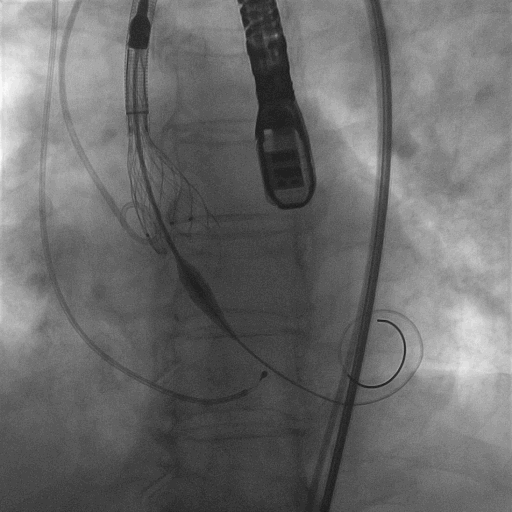

使用VenusA-Plus®回收功能以后,调整投射角度继续以高位释放

再次释放到2/3,造影观察瓣膜位置良好,选择全部释放

L23高位释放成功